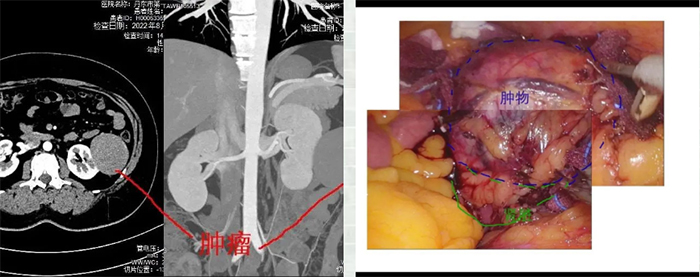

患者女性,年龄50岁,因腰部疼痛不适就医,完善相关查检查后明确诊断为腹膜后肿物。在我市多方寻医后,来到我院求助。我院普外一科接诊后,经过细致的病情分析,告知患者该手术可在腹腔镜下完成,并且目前已经可以成熟开展该类型手术。患者听后,兴奋的说到,“在丹东不仅可以做这种手术,还可以在腹腔镜下完成,我们不需要到北京、上海去了,不但省去奔波劳累,治疗费用更是省了很多,太好了!”

术中发现,该患者的腹膜后肿物,不仅体积大,还与其后腹膜的重要神经血管关系密切,特别是肿瘤已临近肾脏及输尿管,稍有不慎,将出现严重的副损伤。吴瑶强副院长带领手术团队,团结协作、默契配合,最终安全顺利的将肿物完整切除。

术后6小时,患者便离床活动,术后第二天肠道功能恢复,可进流食,三天后顺利出院。